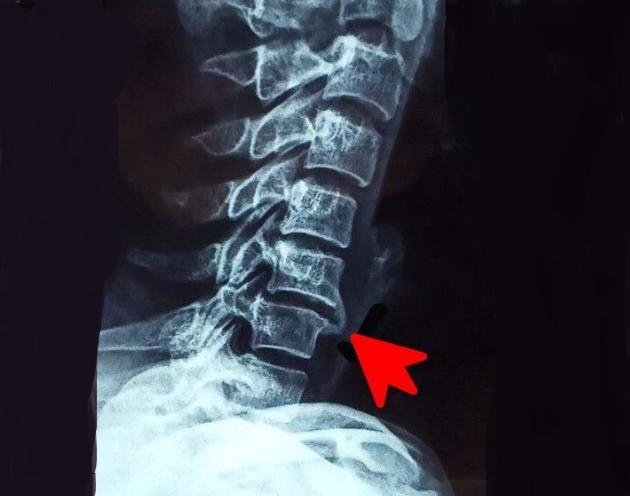

(2)脊椎

有些人长期伏案工作或者总是瘫坐在沙发上,脊柱长时间处于过度负荷状态,容易骨质增生。

一旦椎体表面的骨质增生压迫了附近的神经或血管,就会产生相应的症状。如头晕、脖子疼、腰痛、手麻、腿麻等。此时,椎体的骨质增生已经恶化成颈椎病、腰椎病了,需要及时就医。